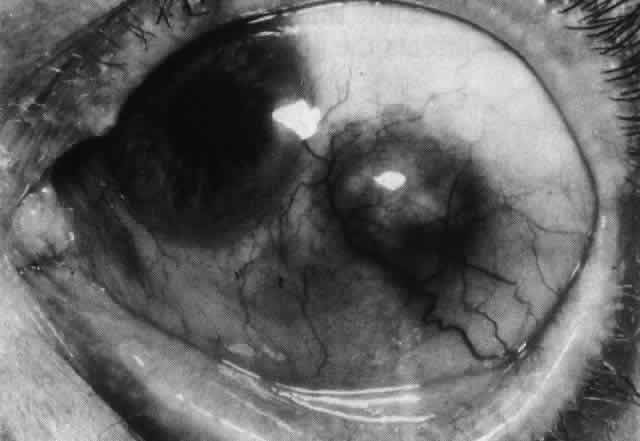

Fig. 43. Late venous phase of angiogram of a patient with necrotizing scleritis

showing late deep leakage from vessels on the surface of the sclera and

leakage of the capillary network at the limbus and the vessels draining

it, together with poor or absent perfusion of the remaining vessels. Fig. 43. Late venous phase of angiogram of a patient with necrotizing scleritis

showing late deep leakage from vessels on the surface of the sclera and

leakage of the capillary network at the limbus and the vessels draining

it, together with poor or absent perfusion of the remaining vessels.

|

The characteristic features of necrotizing scleritis on fluorescein angiography

are hypoperfusion and, eventually, nonperfusion of the vascular

networks (Figs. 40 through 43).26 The initial changes are on the venous side of the capillary network; the

transit time of the dye increases even if the eye is red and congested. If

the disease process persists or has been present for a long time, thrombosis

and permanent vaso-occlusive changes occur. These vessels (or

the occluded capillary network) are bypassed by the opening of

anastomotic channels. New vessels in a granuloma give rise to deep intrascleral

leakage of dye (see Fig. 43). Conjunctival and episcleral involvement by the destructive change is